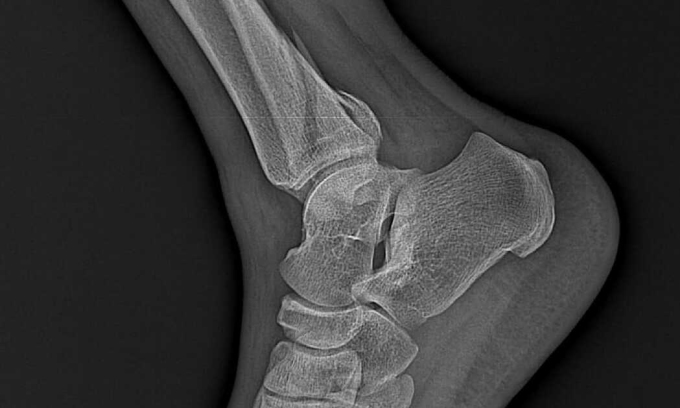

Người phụ nữ sưng nề bàn chân sau khi đắp lá chữa gãy xương

Theo VnExpress, gia đình người phụ nữ 35 tuổi cho biết, 2 tuần trước, bệnh nhân bị trượt ngã gãy xương cẳng chân phải nhưng không đi viện mà nghe người quen mách đắp lá.

Thời gian gần đây, bệnh nhân đau, không vận động được cổ chân phải, sưng nề bàn chân, vùng cổ chân có biểu hiện viêm da, kích ứng, phải nhập Bệnh viện Đa khoa Hùng Vương.

Ngày 19/2, các bác sĩ thông tin nữ bệnh nhân bị gãy 3 mắt cá chân nặng. Vùng cổ chân bị viêm, sưng đỏ do đắp lá không rõ nguồn gốc. Bác sĩ đã làm sạch ổ gãy, đặt lại xương, cố định lại bằng nẹp, vít. Hiện tại, sức khỏe của người bệnh ổn định, tiếp tục vận động để cải thiện tình trạng.

Được biết, gần đây, bệnh viện tiếp nhận nhiều trường hợp uống thuốc nam để chữa ung thư, bỏng nhưng chữa gãy xương thì khá hiếm. Gãy xương là tổn thương bên trong, tuyệt đối không lạm dụng thuốc nam, thuốc không rõ nguồn gốc, kéo dài thời gian điều trị, để lại nhiều biến chứng.

Khi gặp chấn thương, tốt nhất mọi người nên đến bệnh viện hoặc các cơ sở y tế để nhận được tư vấn của bác sĩ chuyên khoa.